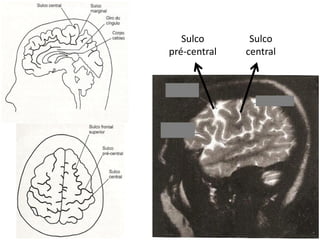

Ressonância Magnética do Crânio

• Sistema de obtenção de

imagens é mais sensível à

natureza molecular dos tecidos;

• Alta densidade tissular não

resulta em resolução de

contraste.

   Doenças da substância branca;

   Neoplasias;

   Doenças infecciosas;

   Distúrbios hemorrágicos;

   Distúrbios isquêmicos.

Sulco       Sulco

pré-central   central